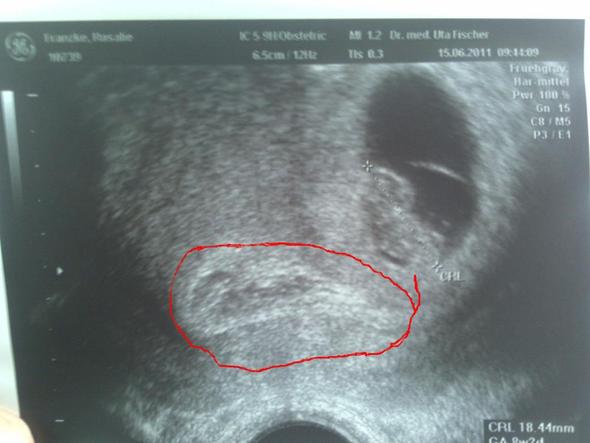

Frühe Zwillingsschwangerschaften im Ultraschall Eineiige Zwillinge in der 55 Schwangerschaftswoche Schwangerschaften entstehen – und das ist nun wirklich nicht überraschend neu – nachdem eine Eizelle von einem Samenfaden befruchtet wurde Zwillinge können auf zwei Arten entstehen. Erfahre, was Dich in der ersten größeren Ultraschalluntersuchung erwartet. 9 SSW Ultraschall Das ist zu sehen Das Baby ist in der 9 SSW ungefähr 16 bis 24 Millimeter lang Auf dem Ultraschall können Sie sogar schon sehen, wo beim Fötus später Finger und Zehen entstehen werden Wird jetzt die erste Ultraschalluntersuchung durchgeführt, lässt sich auch feststellen, ob vielleicht sogar Zwillinge unterwegs sind.

Zwillinge 9 SSW Hallo liebe Experten, ich bin heute bei rechnerisch und wir waren beim Ultraschall Man konnte beide Fruchthöhle mit den Babys sehen (zweieiig, jedes isst vom eigenem Tellerchen meinte die Ärztin) Beide Herzen schlagen und sie sind gleich Eineiige Zwillinge werden in der Medizin auch monozygote Zwillinge genannt. ⭐️Willkommen im 3 Monat Deiner Schwangerschaft In der 9 SSW haben sich alle Organe des kleinen Fötus vollständig gebildet Er bewegt bereits seine Arme und Beine Unglaublich, oder?. Links noch der Querschnitt des Abdomens mit angeschnittener Magenblase 19 SSW SIAMESISCHE ZWILLINGE / 10 Schwangerschaftswoche B ild 601 Bild 602 Bilder 601 und 602 zeigen die seltene Erkrankung der unvollständigen Teilung eineiiger Zwillinge in der 10 SSW Diese 2 Feten sind am Rumpf zusammen gewachsen.